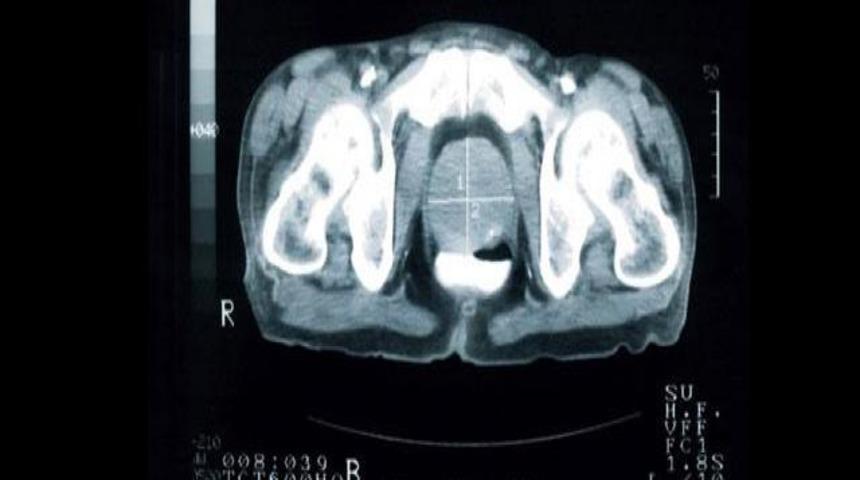

Lazer teknolojisi ile son sistem ultrasonun birleştirildiği bir mikrokop geliştiren Kolios, ultrason sayesinde elde ettiği yüksek frekanstaki seslerle lazer ışınlarını birleştirip, kandaki farklı hücrelerin fotoğraflarını çekti. Hücrelerin ses ve ışın yansımalarını analiz etmede sağlanan gelişme, özellikle kan kanserinin erken teşhisinde önemli bir adım olarak nitelendirildi.